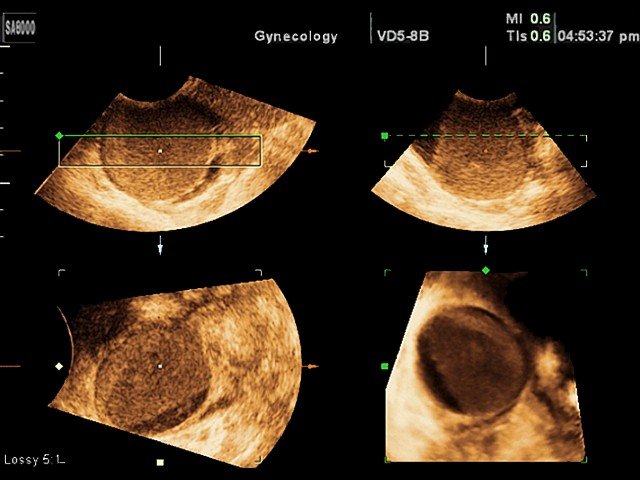

Ovarian cyst, 3D

Ovarian cyst, 3D (echogramm №344)

[RU] Ultrasound image №344: Ovarian cyst in 3D mode.

Echogramm was received by ultrasound scanner SonoAce-8000 (out of production).